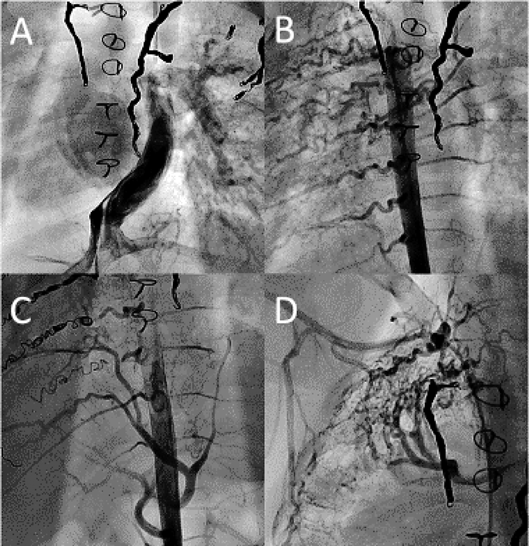

Fig. 4 Cine angiograms of the case

An inferior vena cava angiogram demonstrates that only the left pulmonary artery was imaged, and no contrast agent flowed into the right pulmonary artery (A). An aortogram shows the large intercostal arteries and inferior phrenic artery (B and C). A right subclavian artery angiogram demonstrates many aortopulmonary collateral arteries (D).

平均中心静脈圧は20 mmHg,左右の平均肺動脈楔入圧は16と37 mmHgで,心係数は1.82 L/min/m2,肺体血流比は2.88であった.下大静脈造影は造影剤が左肺動脈にのみ還流した(Fig. 4A).右鎖骨下動脈や下行大動脈造影は右側へ向かう多量の体肺側副血管を認め(Figs. 4B, C, D),右肺動脈に還流した血液は全て左肺動脈へ逆行した.